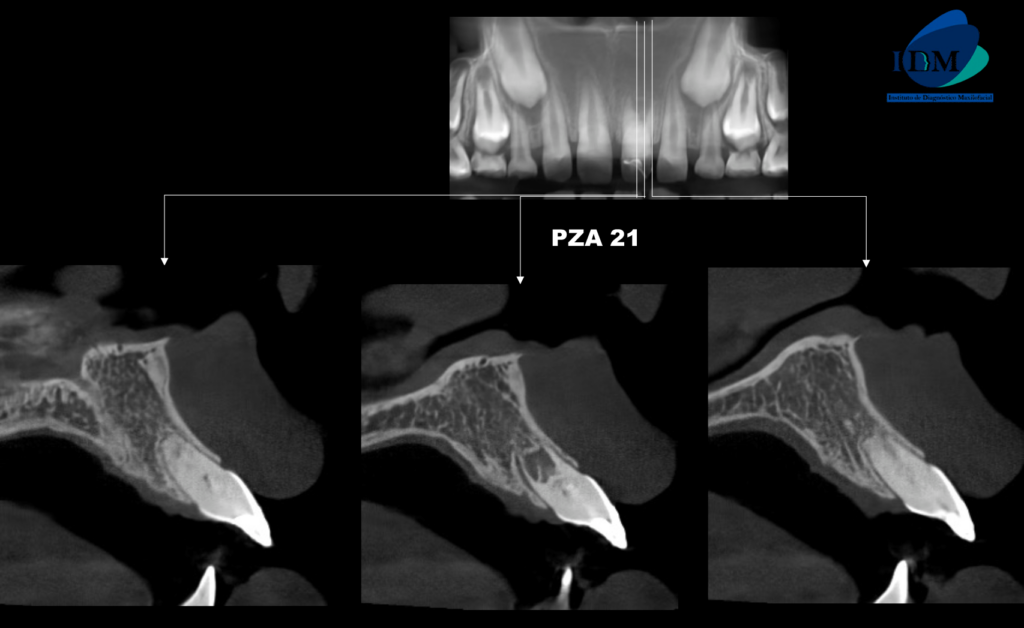

En la radiografía panorámica (Figura 1), se observa pieza 21 con material restaurador coronal, obliteración parcial cámara y conducto radicular.

Radiografia Panorámica

A la evaluación de la tomografía volumétrica (cone beam) de campo reducido en los cortes axiales (Figura 2) y transaxiales (Figura 3) se observa la pieza 21 con material restaurador coronal, obliteración de cámara y conducto radicular en tercio cervical y medio; además de observar la formación radicular incompleta caracterizado por tercio apical de conducto y foramen apical amplio; signos compatibles con secuela de trauma dental.

CORTES TRANSAXIALES